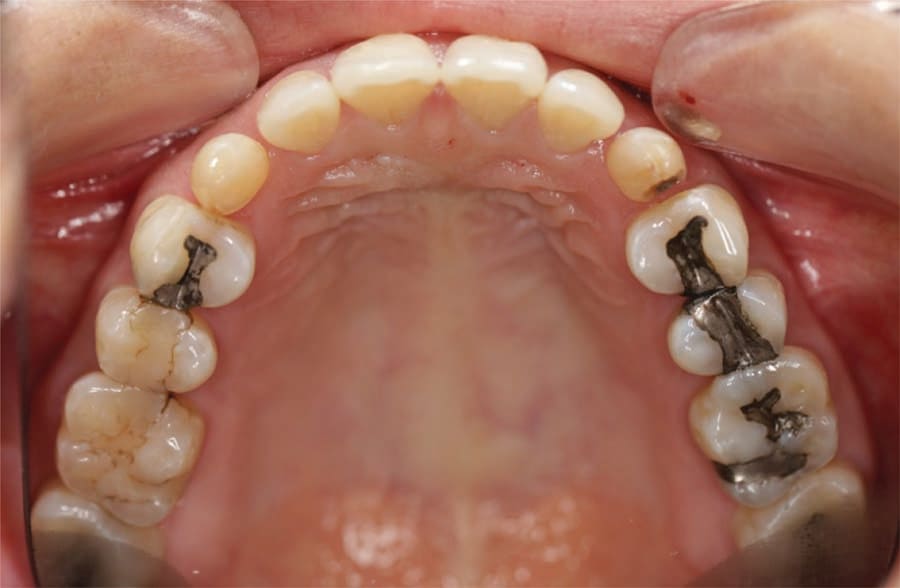

A 31-year-old Asian female presented for a consult. Her medical history was reviewed, and no health issues were noted. She indicated her last dental visit was 2 years ago and her chief complaint was that her deciduous canines felt loose and she was unhappy with her smile (Figure 1). Examination noted fair oral hygiene with light generalized calculus and moderate bleeding in the posterior with 4 mm probing on the molars. The deciduous canines were present bilaterally in the maxilla which were grade 1+ mobile (Figure 2). Cervical caries was noted on both deciduous teeth on the facial and also the distal of the left deciduous canine (Figure 3). Tooth No. 28 (right mandibular first premolar) was noted to be missing. The patient indicated the missing bicuspid never developed and the deciduous molar was lost in her teens. Physical examination noted a concavity in the vestibule apical to the gingival margin at both canine sites. A panoramic and bitewing radiographs were taken to evaluate the dentition and arches (Figure 4). Radiographically it was confirmed that the permanent maxillary canines were not present nor was the mandibular bicuspid. Further, significant resorption of the roots of the deciduous canines was noted.